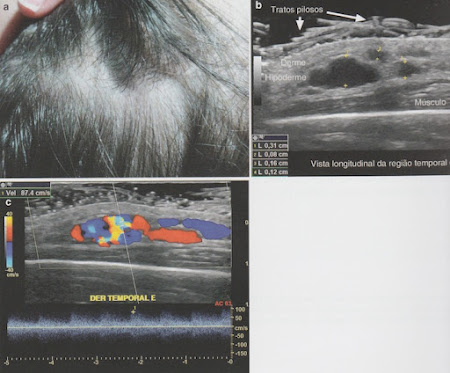

Malformação Vascular Arterial de Alto Fluxo

Achados:

- Estruturas tubulares anecóicas, tortuosas ou áreas lacunares.

- Fluxo mostra picos sistólicos e diastólicos.